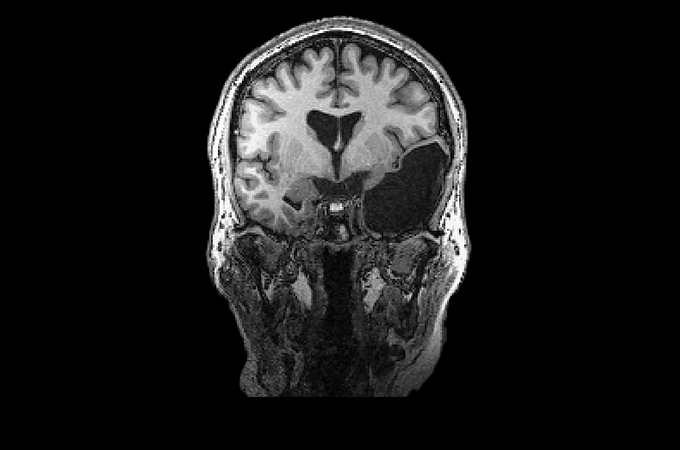

Elyse G. found out she lacked most of her left temporal lobe when she was 25 years old. The brain region is typically crucial for speech and language — but until her brain was scanned (three views shown), no one knew Elyse was missing hers.

Looking at her brain scans is a different story. It’s as if someone has knocked over a bottle of ink. The darkness pools inside her skull near her left ear, a puddle of fuliginous black. Inside the splotch, there’s no white matter or gray matter, no blood vessels or tissue at all.

Elyse says you don’t have to be a neurosurgeon to spot what’s different about her brain: “There’s a big honking piece missing!”